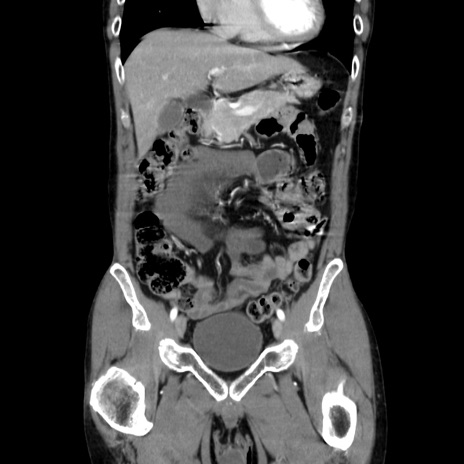

症例37(冠状断像)

【症例】40歳代 男性

【主訴】腹痛

【現病歴】4時間ほど前に電車に乗車中に臍部上より腹痛出現。徐々に増悪し起立困難となり、救急外来受診。生ものは数日食べていない。今朝お雑煮を食べた。

【身体所見】BT 36.8℃、BP 117/84mmHg、HR 91/min、SpO2 97%、苦悶様、腹部:臍上部広範囲圧痛あり、反跳痛±

【データ】WBC 8100、CRP 0.03